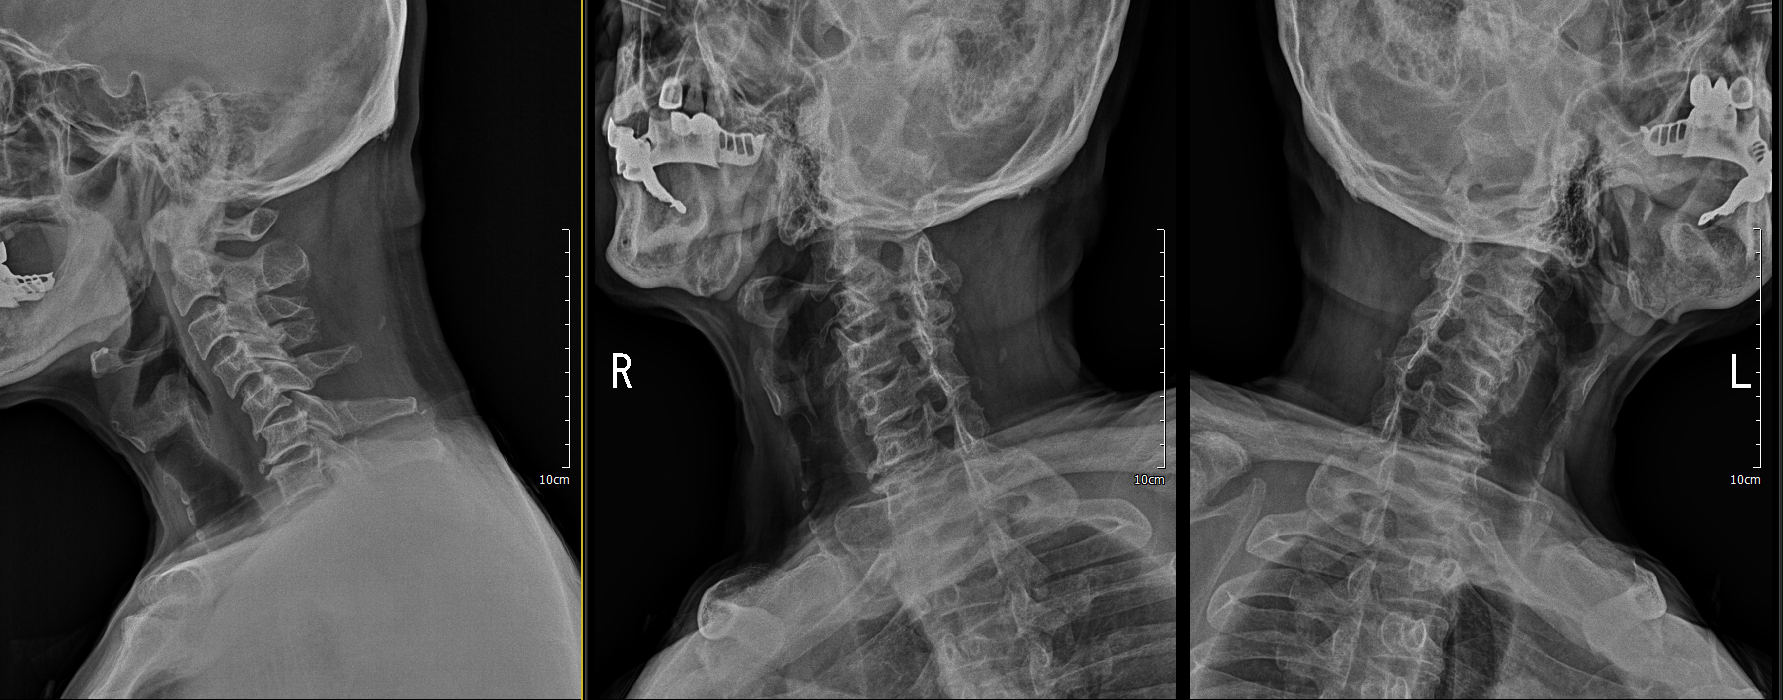

x ray 측면에서 보면 경추 5/6 후관절 탈골이 확인이 됨.

그 다음날에 점심정도에 다시 병원에 오셔서 수술 정하셨다고 하여, 수술방에 올라가 reduction 시행함

reduction 된 것을 확인 하였음.